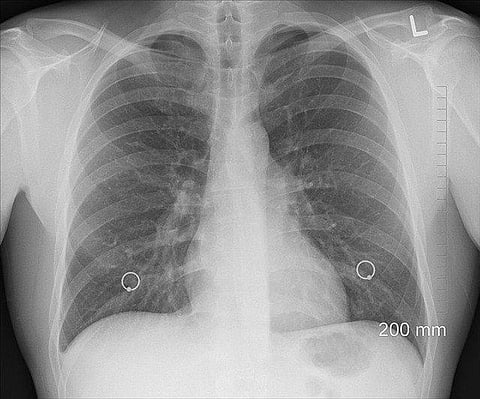

The researchers say the cells might be responsible for the chemical hypersensitivity that characterizes respiratory diseases, such as chronic obstructive pulmonary disease (COPD) and asthma. Patients with these diseases are told to avoid traffic fumes, pungent odors, perfumes, and similar irritants, which can trigger airway constriction and breathing difficulties.

The different mechanisms explain why cognition plays a much stronger role in taste and smell than in coughing in response to an irritant. It is possible, for example, to develop a taste for beer. But nobody learns not to cough; the response is rapid and largely automatic. Scientists suspect these pulmonary neurosecretory cells contribute to the hypersensitivity of patients with COPD to airborne irritants. COPD is a group of diseases, including emphysema, that is characterized by coughing, wheezing, shortness of breath, and chest tightness.

When the scientists looked at the airway tissues from patients with COPD, they discovered that they had more of these neurosecretory cells than airway tissues from healthy donors. Ben-Shahar is hopeful that the PNEC pathways will provide targets for drugs that would better control asthma, COPD, and other respiratory diseases. They would be welcome. There has been a steep rise in these diseases in the past few decades, treatment options have been limited, and there are no cures. (VOA/JC)